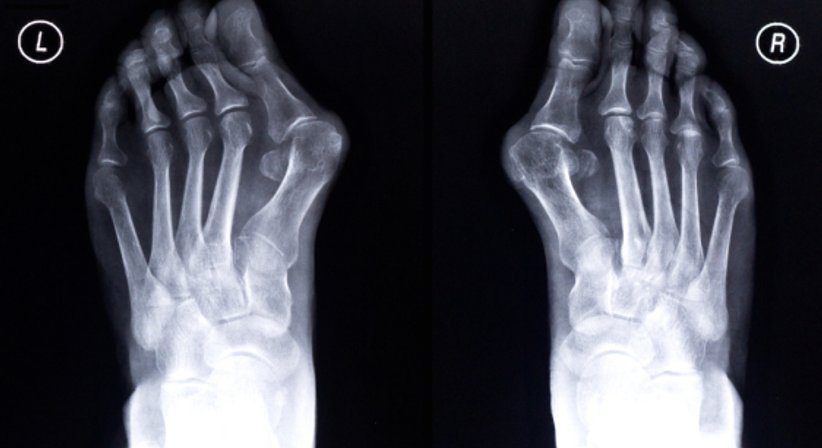

01. Hallux valgus

Ein Hallux valgus, auch Ballenzeh genannt, ist eine Fehlstellung, bei der sich der Mittelfußknochen nach außen bewegt und die Großzehe zu den Mittelzehen. Die Bildung eines Hallux valgus wird durch das tragen hochhackiger und spitz zulaufender Schuhe begünstigt. Als Folge wird das Großzehengrundgelenk stärker abgenutzt. Einlagen und orthopädische Schuhe helfen, die Schmerzen in den Zehen zu verringern. Der Hallux valgus bildet sich jedoch durch diese Behandlung nicht zurück. Das kann nur durch eine Operation erreicht werden, bei der die Stellung der Großzehe korrigiert wird.